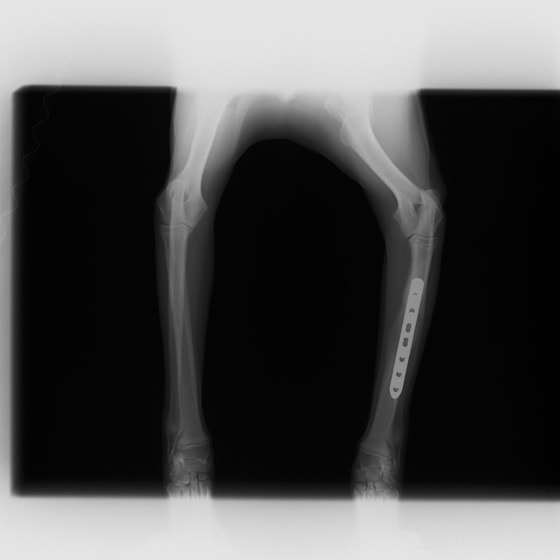

症例3:キルシュナーワイヤーのピンニングによる整復

ペルシャ猫 11ヶ月齢 雄

他院にて左大腿骨遠位の成長板骨折(salter-harrisⅠ型)が認められており、治療相談を目的として来院。当院にて、キルシュナーワイヤーを用いたピンニングにより骨折部位の整復を行いました。術後の経過は良好で、現在も経過観察中です。

術前レントゲン

術後レントゲン

Arthrex社のターゲティングデバイスを用いてピンニングの位置を調整することで、確実な固定を行っています。当院ではこの手術器具以外にも、人の手術にも使用される様々な器具を導入し、手術精度を高め、また医療メーカーと新しい器具の開発、試作にも取り組んでおります。